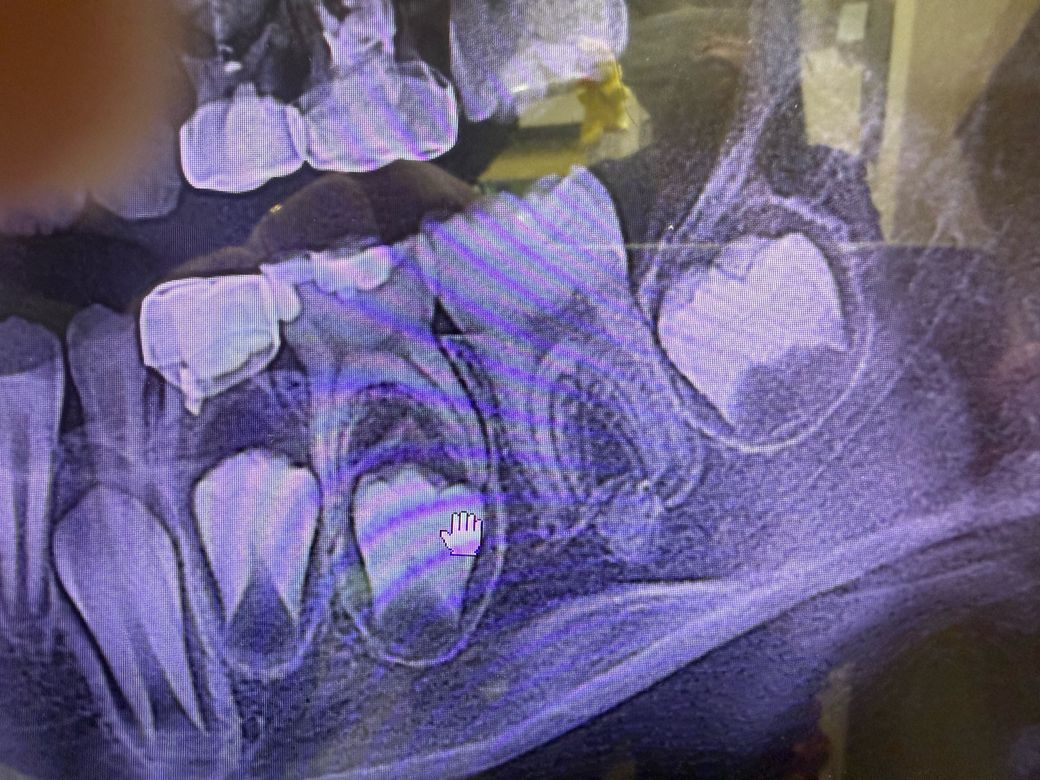

아이가 치아 골경화 의심되는데 걱정입니다

10세 아이 치과 정기검진 갔는데 왼쪽 아래 어금니쪽에 골경화가 의심되는게 있다고 하는데, 선생님은 9개월 후 사진을 다시 찍어보자고 하시네요. 부모로서 걱정이

많이 됩니다. 1) 저런 케이스가 많은지 2) 안좋은 상환으로도 갈 가능성이 있는지 궁금합니다.

• 1번 째 사진

경우에 따라서는 치조골이 경화가 되는 경우가 있습니다. 또한 외골증등으로 인해서 해당부위의 골밀도가 높게 보이는 경우도 있습니다.

idiopathic sclerosis dental 이라고 검색해보세요. 말 그대로 특발성(원인을 알 수 없는)인거고 굳이 치료가 필요하지 않습니다. 그냥 꾸준히 추적관찰 하시면 됩니다.